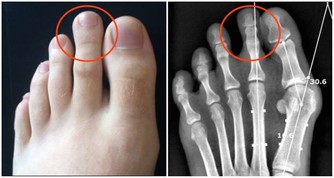

接下來說說足廯導致的腳癢問題~

足癬是一種接觸傳染性皮膚病。如果接觸了帶真菌的腳、鞋襪、拖鞋、毛巾和水等,真菌數量比較多,毒力比較強,接觸者的皮膚又比較潮濕,就容易被傳染。

那麼,足廯能徹底治好嗎?

答案是肯定的。

患足廯的人經常吐槽,“足癬年年治,足癬歲歲發”。之所以會這樣,根本原因在於治療不徹底。很多人治足廯時,症狀一緩解,就沒耐心用藥了。

實際上,根治足癬,首先應建立在合理、規範治療的基礎上,不要症狀一緩解就停藥。